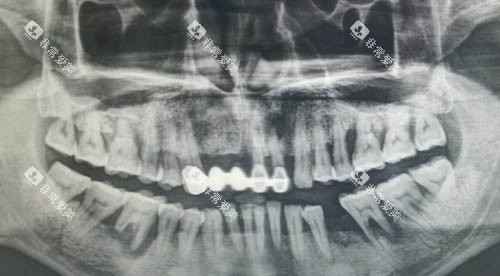

从临床应用的情况来看,大清西格种植牙已经在众多口腔医疗机构得到了广泛的应用。

许多患者在接受大清西格种植牙手术后,都取得了良好的治疗结果。他们反馈种植牙的舒适度高,咀嚼功能修复良好,外观也非常自然。

同时,医生们也对大清西格种植牙的性能给予了肯定,认为它在操作过程中比较方便,稳定性好,能够满足不同患者的需求。